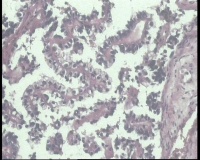

| 一般病史 | 彩超:盆腔可见囊实性回声,囊性为主,大小约5.0x3.7厘米,其内可见分隔回声,部分分隔内回声不纯净,形态欠规整 | ||||

| 标本名称 | 腔镜下右侧卵巢囊肿手术 | ||||

| 大体所见 | 囊壁样组织5.5x5.0厘米,4.5x2.5厘米2块,壁厚0.1-0.2lm,囊壁大部分光滑,局灶见0.7x0.5x0.3厘米淡黄色突起组织,另见淡黄色、肉粉色质软组织2.8厘米一堆。 | ||||